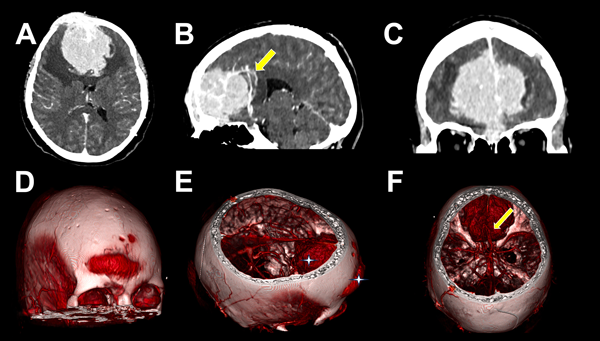

Figura 1. A, B, C) TC contrastada y angioTC preoperatoria. A) Lesión extraaxial, circunscripta, en topografía del surco olfatorio, con realce homogéneo a la administración de contraste y edema vasogénico perilesional. B) Desplazamiento de arterias pericallosas y rodilla del cuerpo calloso hacia posterior (flecha amarilla). C) En corte coronal se evidencia base de implantación frontobasal y desplazamiento de polos frontales hacia lateral. D, E, F) TC con reconstrucción 3D. D) Componente exofítico transcraneano bifrontal. E) Compromiso extra e intracraneal de lesión (cruces blancas). F) Lesión voluminosa e hipervascularizada, se evidencian arterias pericallosas desplazadas hacia posterior (flecha amarilla).

Se han descripto dos patrones de extensión, la diseminación hematógena de células plasmáticas y la diseminación continua directa desde lesiones líticas erosionadas del cráneo.1,12 En cuanto al diagnóstico diferencial, destacan las similitudes imagenológicas con los meningiomas, tumores que surgen de las células aracnoideas de la duramadre y constituyen una de las neoplasias intracraneales más comunes. En RM suelen verse como una masa extraaxial redondeada de bordes suaves y circunscrita con base ancha en la superficie dural, presentan hipointensidad en secuencia T1 e hiperintensidad en secuencia T2 con realce homogéneo a la administración de contraste y el signo de “cola dural” que no es patognomónico de esta entidad y puede advertirse en otras lesiones como hemangiopericitoma, metástasis o linfomas; esto hace casi indistinguible la diferenciación preoperatoria en casos como este (ver Figuras 1 y 2).